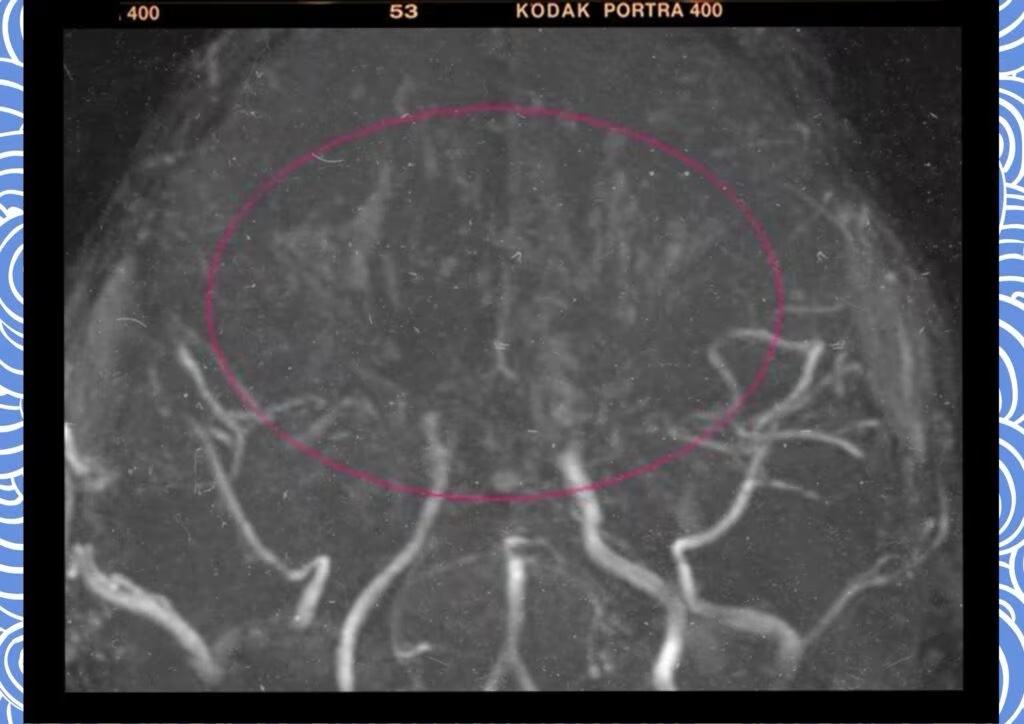

모야모야병은 뇌기저부의 주요 혈관이 서서히 협착되고 막히면서 뇌혈류가 감소하는 만성 진행성 뇌혈관 질환입니다. 협착이 진행된 부위를 대신해 뇌는 생존을 위해 얇고 약한 혈관망을 만들어 혈류를 보충하려 하고, 이 새로운 혈관들이 촬영 영상에서 연기처럼 퍼져 보인다고 하여 ‘모야모야’라는 이름이 붙었습니다. 기전적으로는 내경동맥 말단부와 중대뇌동맥·전대뇌동맥의 기시부에 병변이 가장 잘 생기며, 시간이 지남에 따라 양쪽에 대칭적으로 나타나는 특징을 보였습니다. 이 질환은 단순한 혈관 협착이 아니라 진행성 변화이기 때문에 치료하지 않으면 혈류 부족이 심해지고 뇌 손상이 누적될 수 있습니다. 또한 뇌기능이 체력·호흡·체온 변화 등에 민감하게 반응하기 때문에 과호흡, 울음, 격렬한 운동, 감염 등으로 증상이 악화될 수 있습니다. 즉, 모야모야병은 시간이 지나면서 뇌혈류를 감소시키고 뇌졸중 위험을 높이는 질환이며, 평생 관리가 필요한 만성적 특성을 갖고 있습니다.

따라서 가족력이 있거나 의심되는 증상이 있다면 뇌 MRA·MRI 등의 정기검진이 도움이 되며, 조기 진단 시 치료 효과도 훨씬 높아집니다.